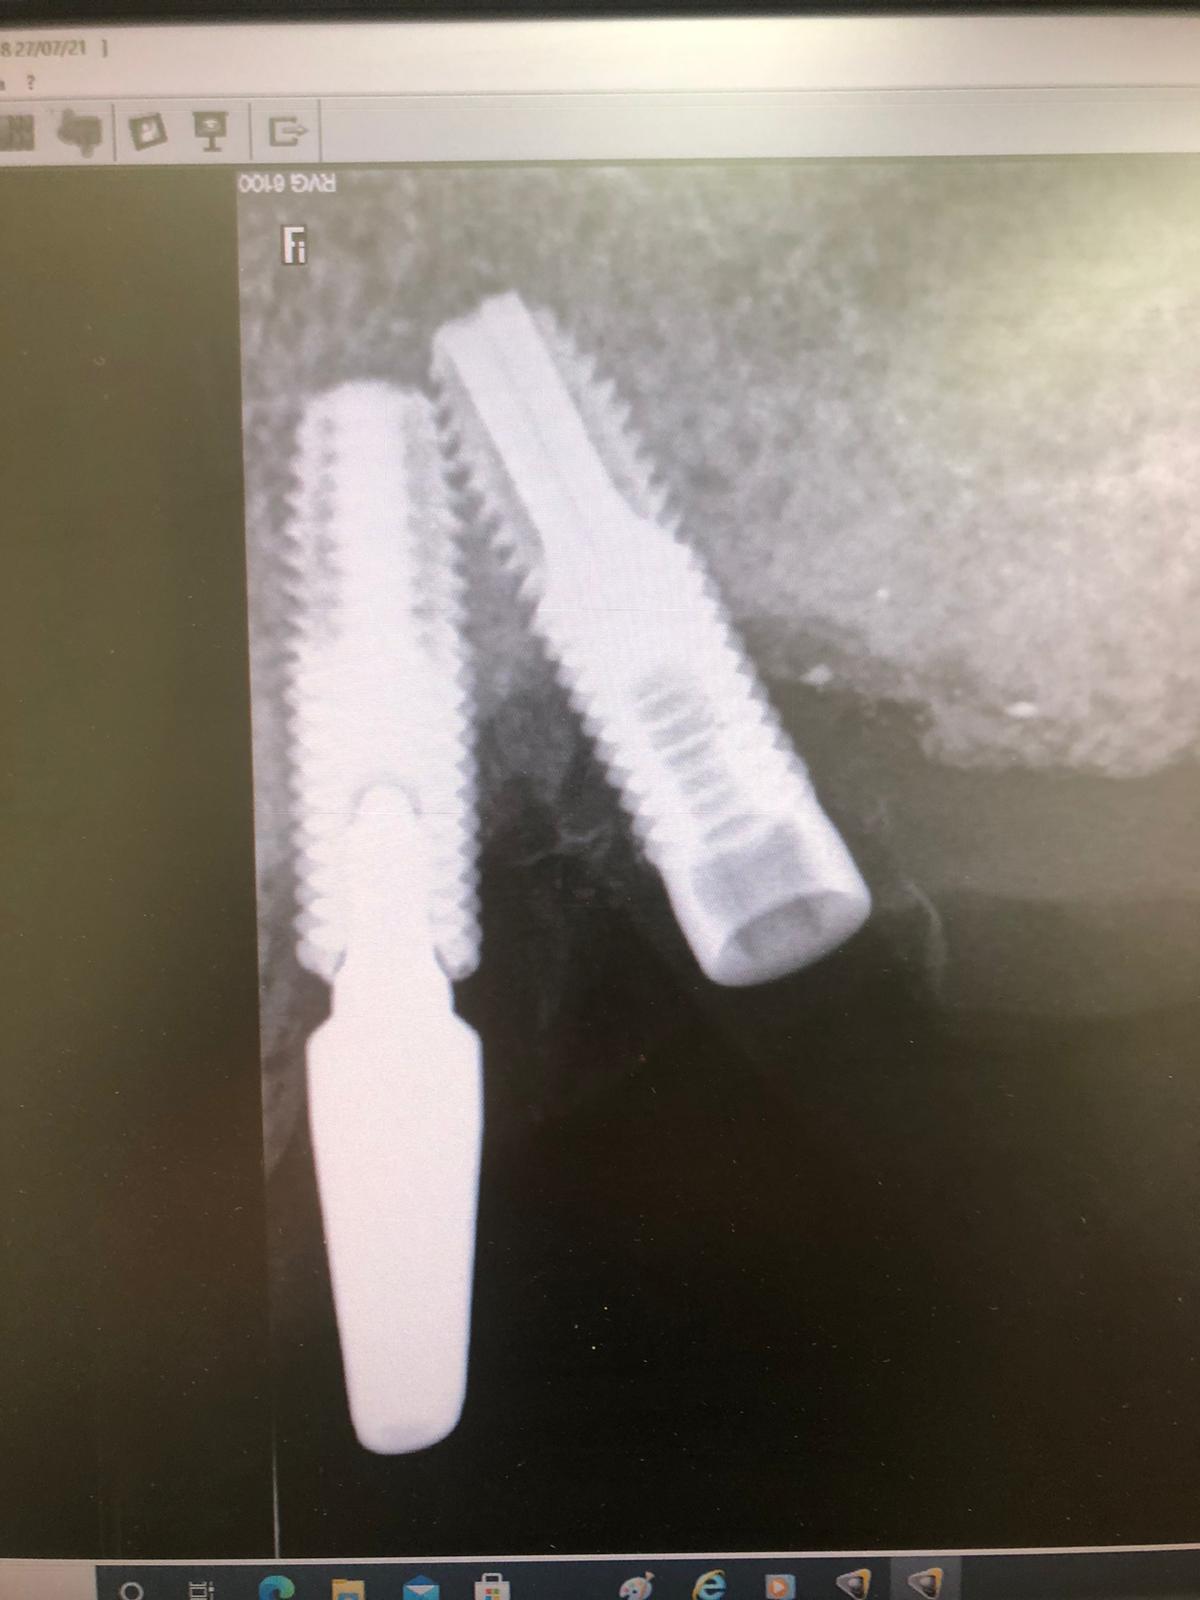

El paciente es un gran bruxómano y rompió hace tres años el implante Mesial (flecha en la imagen), pero no rompió solo la rosca del aditamento, sino también la cabeza del implante entera, quedando solo un resto de hueco roscado (comparar la anatomía de los implantes) en el que lo único que se pudo hacer, debido a que el implante tenía la conexión rota, fue roscar el aditamento ASATIM, pero solo la zona roscada y no el refuerzo y cono del implante, el cual había desaparecido (flecha en la imagen).

En nuestra clínica pusimos un aditamento de tornillo pasante en el implante distal. Y con esto se rehízo la prótesis. Así ha estado hasta este momento en el que aparece con la rosca de este tornillo pasante distal roto y dentro del implante (círculo en la imagen).